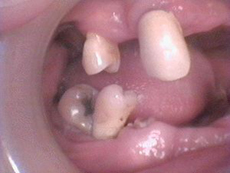

もうぼろぼろです。どこで噛んでいるのかわかりません。とても気の毒です。